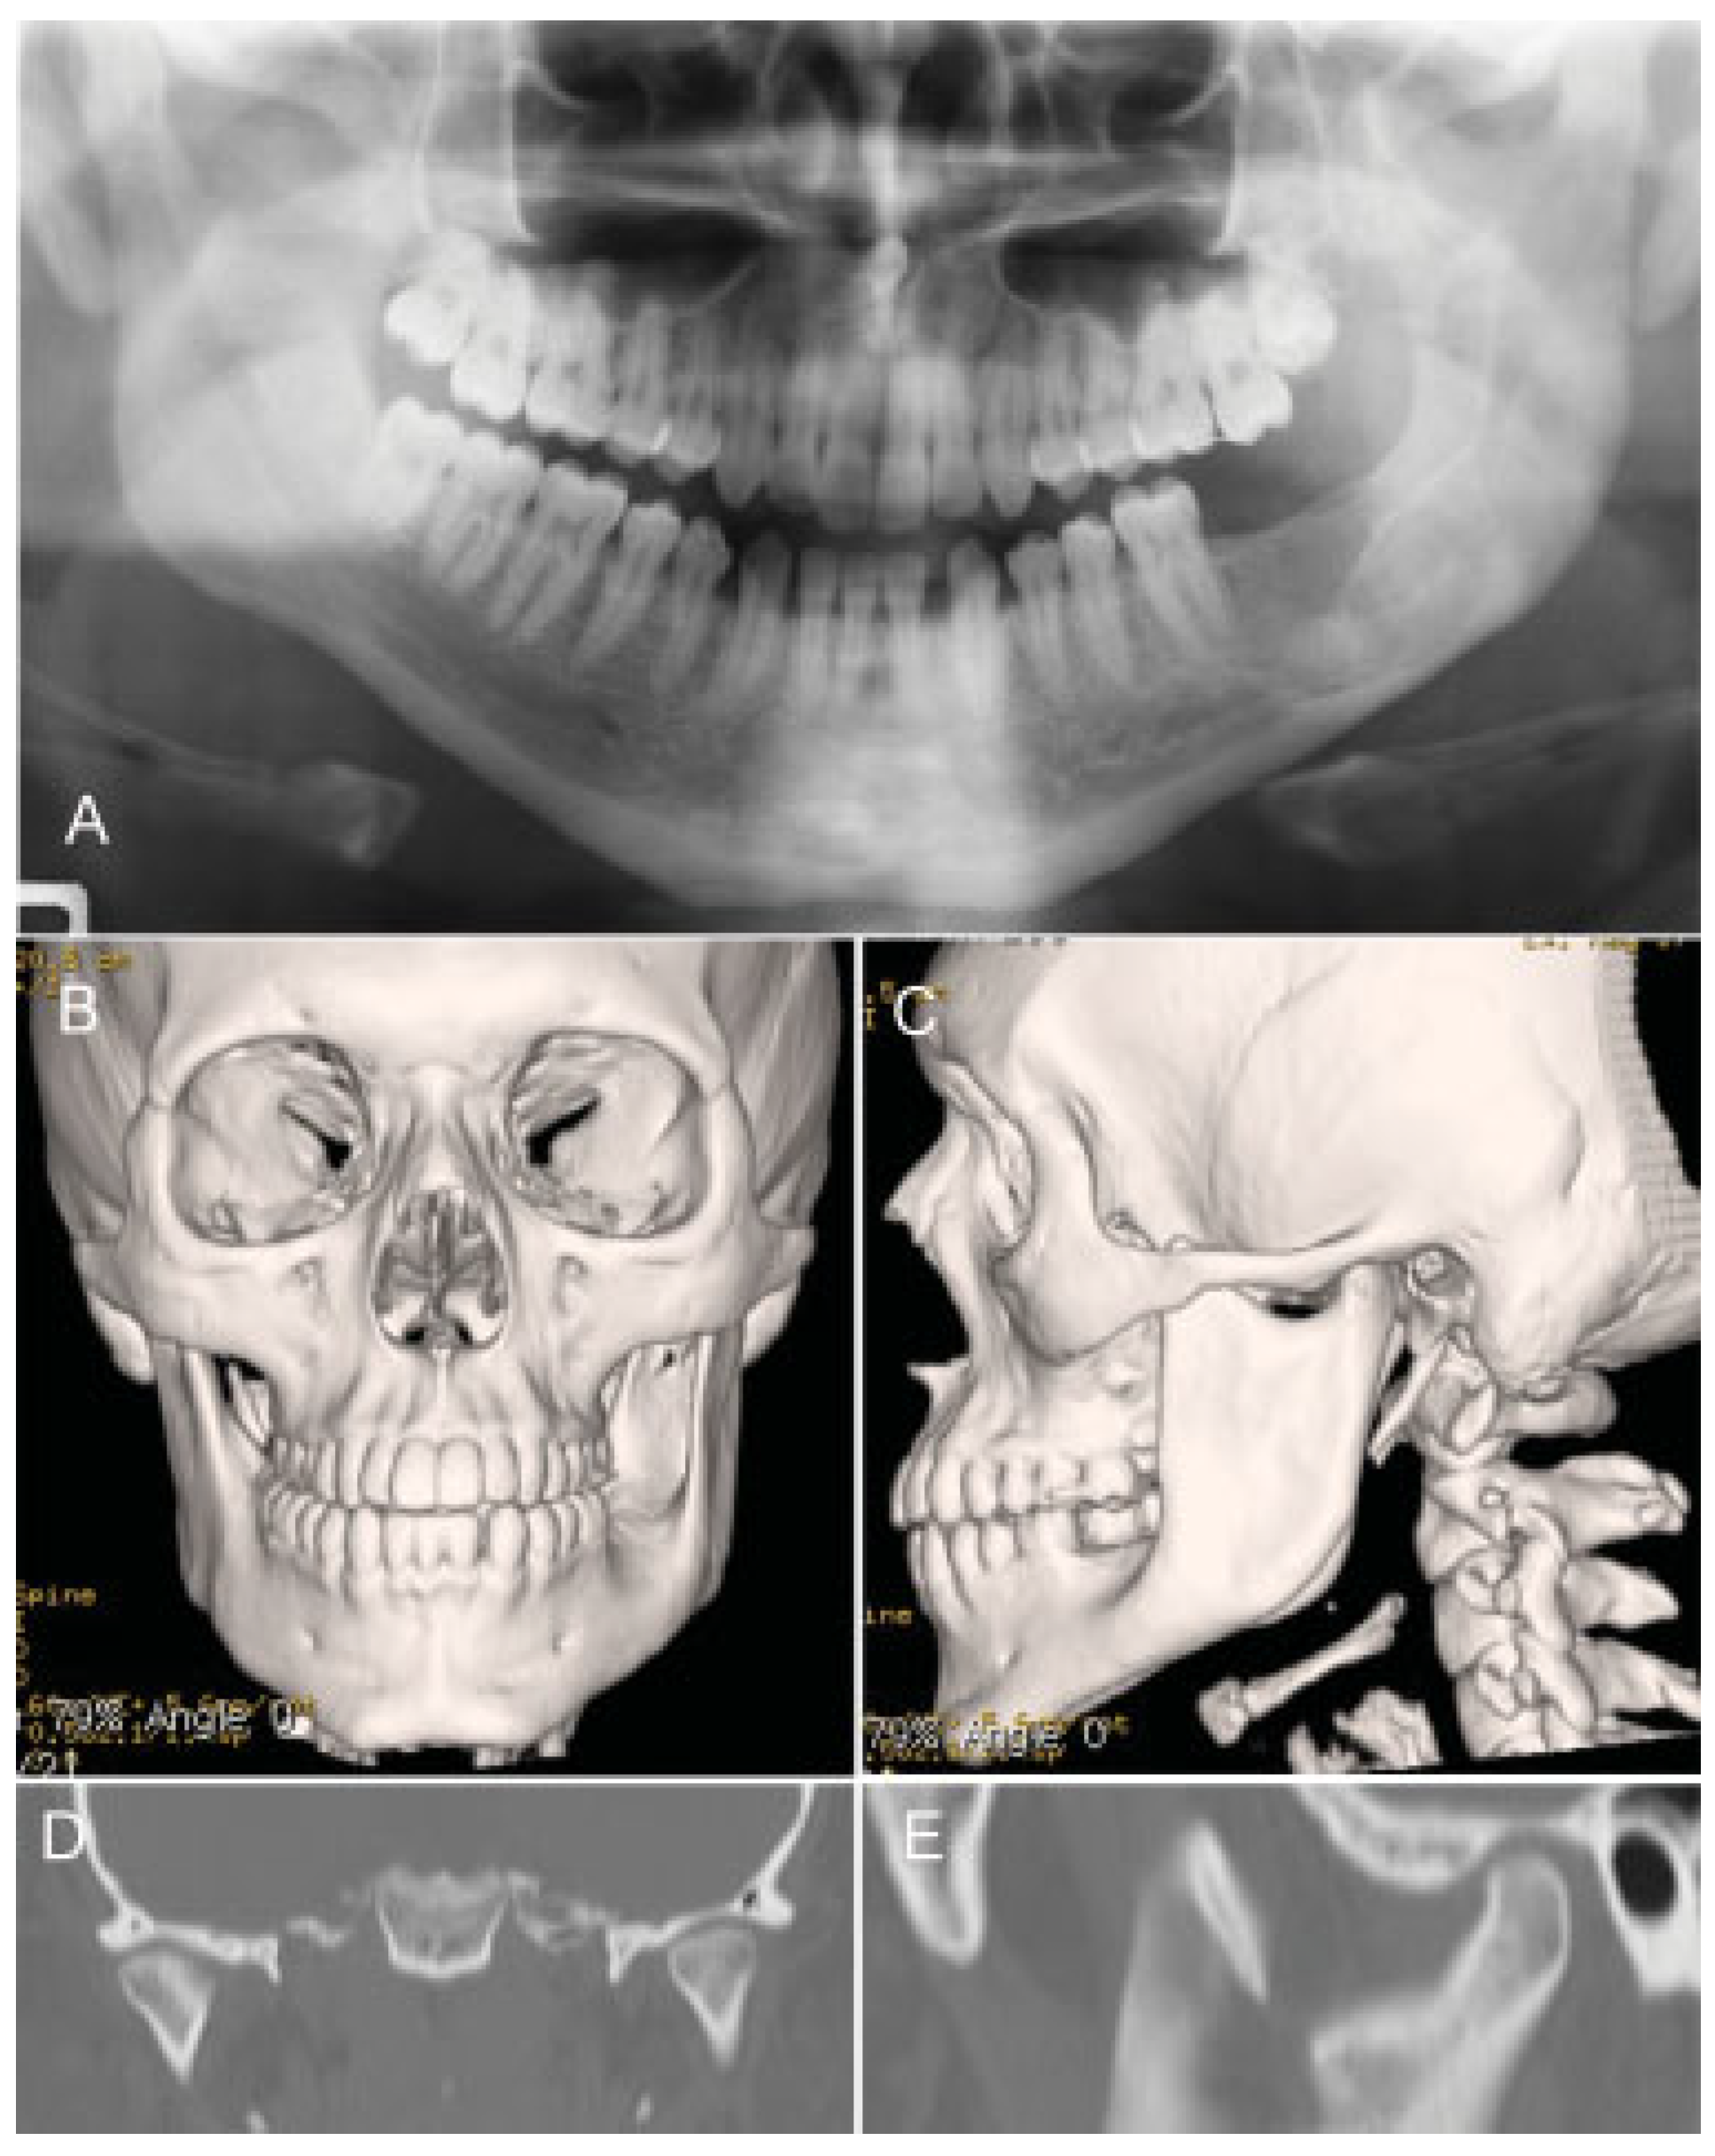

Two Stage Enucleation and Deflation of a Large Unicystic Ameloblastoma with Mural Invasion in Mandible

Case Report